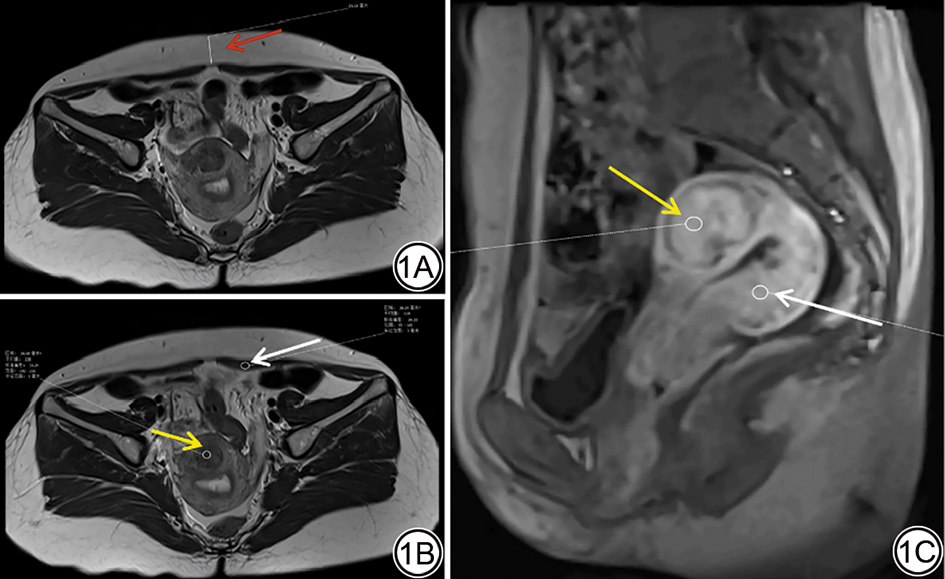

HIFU术后6个月时进一步比较HIFU治疗前后子宫肌瘤复生长患者的MRI参数发现,复生长患者的Ktrans值和iAUC值增加,两组间差异具有统计学意义(P<0.05)(图2表4)。

图2  女,40岁,子宫肌瘤患者接受HIFU治疗,术后6个月肌瘤再次生长。矢状位T1WI DCE-MRI示,治疗前子宫肌瘤(2A;红箭)和HIFU治疗后6个月时肌瘤复发(2B;黄箭),在肌瘤区域内绘制感兴趣区(ROI),分析MRI定量参数Ktrans、Kep、Ve和iAUC值(2C~2D)。

Fig. 2  A 40-year-old female patient diagnosed with uterine fibroids underwent HIFU treatment, and the fibroids regrew 6 months after the operation. Sagittal T1WI dynamic contrast-enhanced MRI shows the uterine fibroids before treatment (2A, red arrow) and the recurrent fibroids 6 months after HIFU treatment (2B, yellow arrow), regions of interest (ROIs) are drawn in the fibroid area to analyze the quantitative parameters of MRI, and the Ktrans, Kep, Ve, and iAUC values are obtained (2C and 2D).